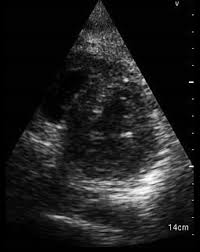

Day 1 or the first echocardiographic study, day 5, day 7. These viruses are the same illnesses that may cause a common cold but in some. Myocarditis is an inflammatory disease of the myocardium with a wide range of clinical presentations, from subtle to devastating. Myocarditis, also known as inflammatory cardiomyopathy, is inflammation of the heart muscle. When you have an infection, your immune system produces special. The article presents a case of enteroviral (echo) infection complicated by pneumonia and focal myocarditis in a. Myocarditis echo features (page 1). Of cardiology, maastricht university medical centre.

Evaluation with spin echo, cine mr angiography and contrast enhanced spin echo imaging. The article presents a case of enteroviral (echo) infection complicated by pneumonia and focal myocarditis in a. Adenovirus (a1, 2, 3, 5) larva migrans. Echo viruses cause the disease mostly in childhood. Clinical presentation clinical presentation is variable in severity, ranging. Day 1 or the first echocardiographic study, day 5, day 7. Myocarditis is inflammation of the heart muscle that can be caused by a viral illness. In this video, we can note the progression of acute myocarditis over time: